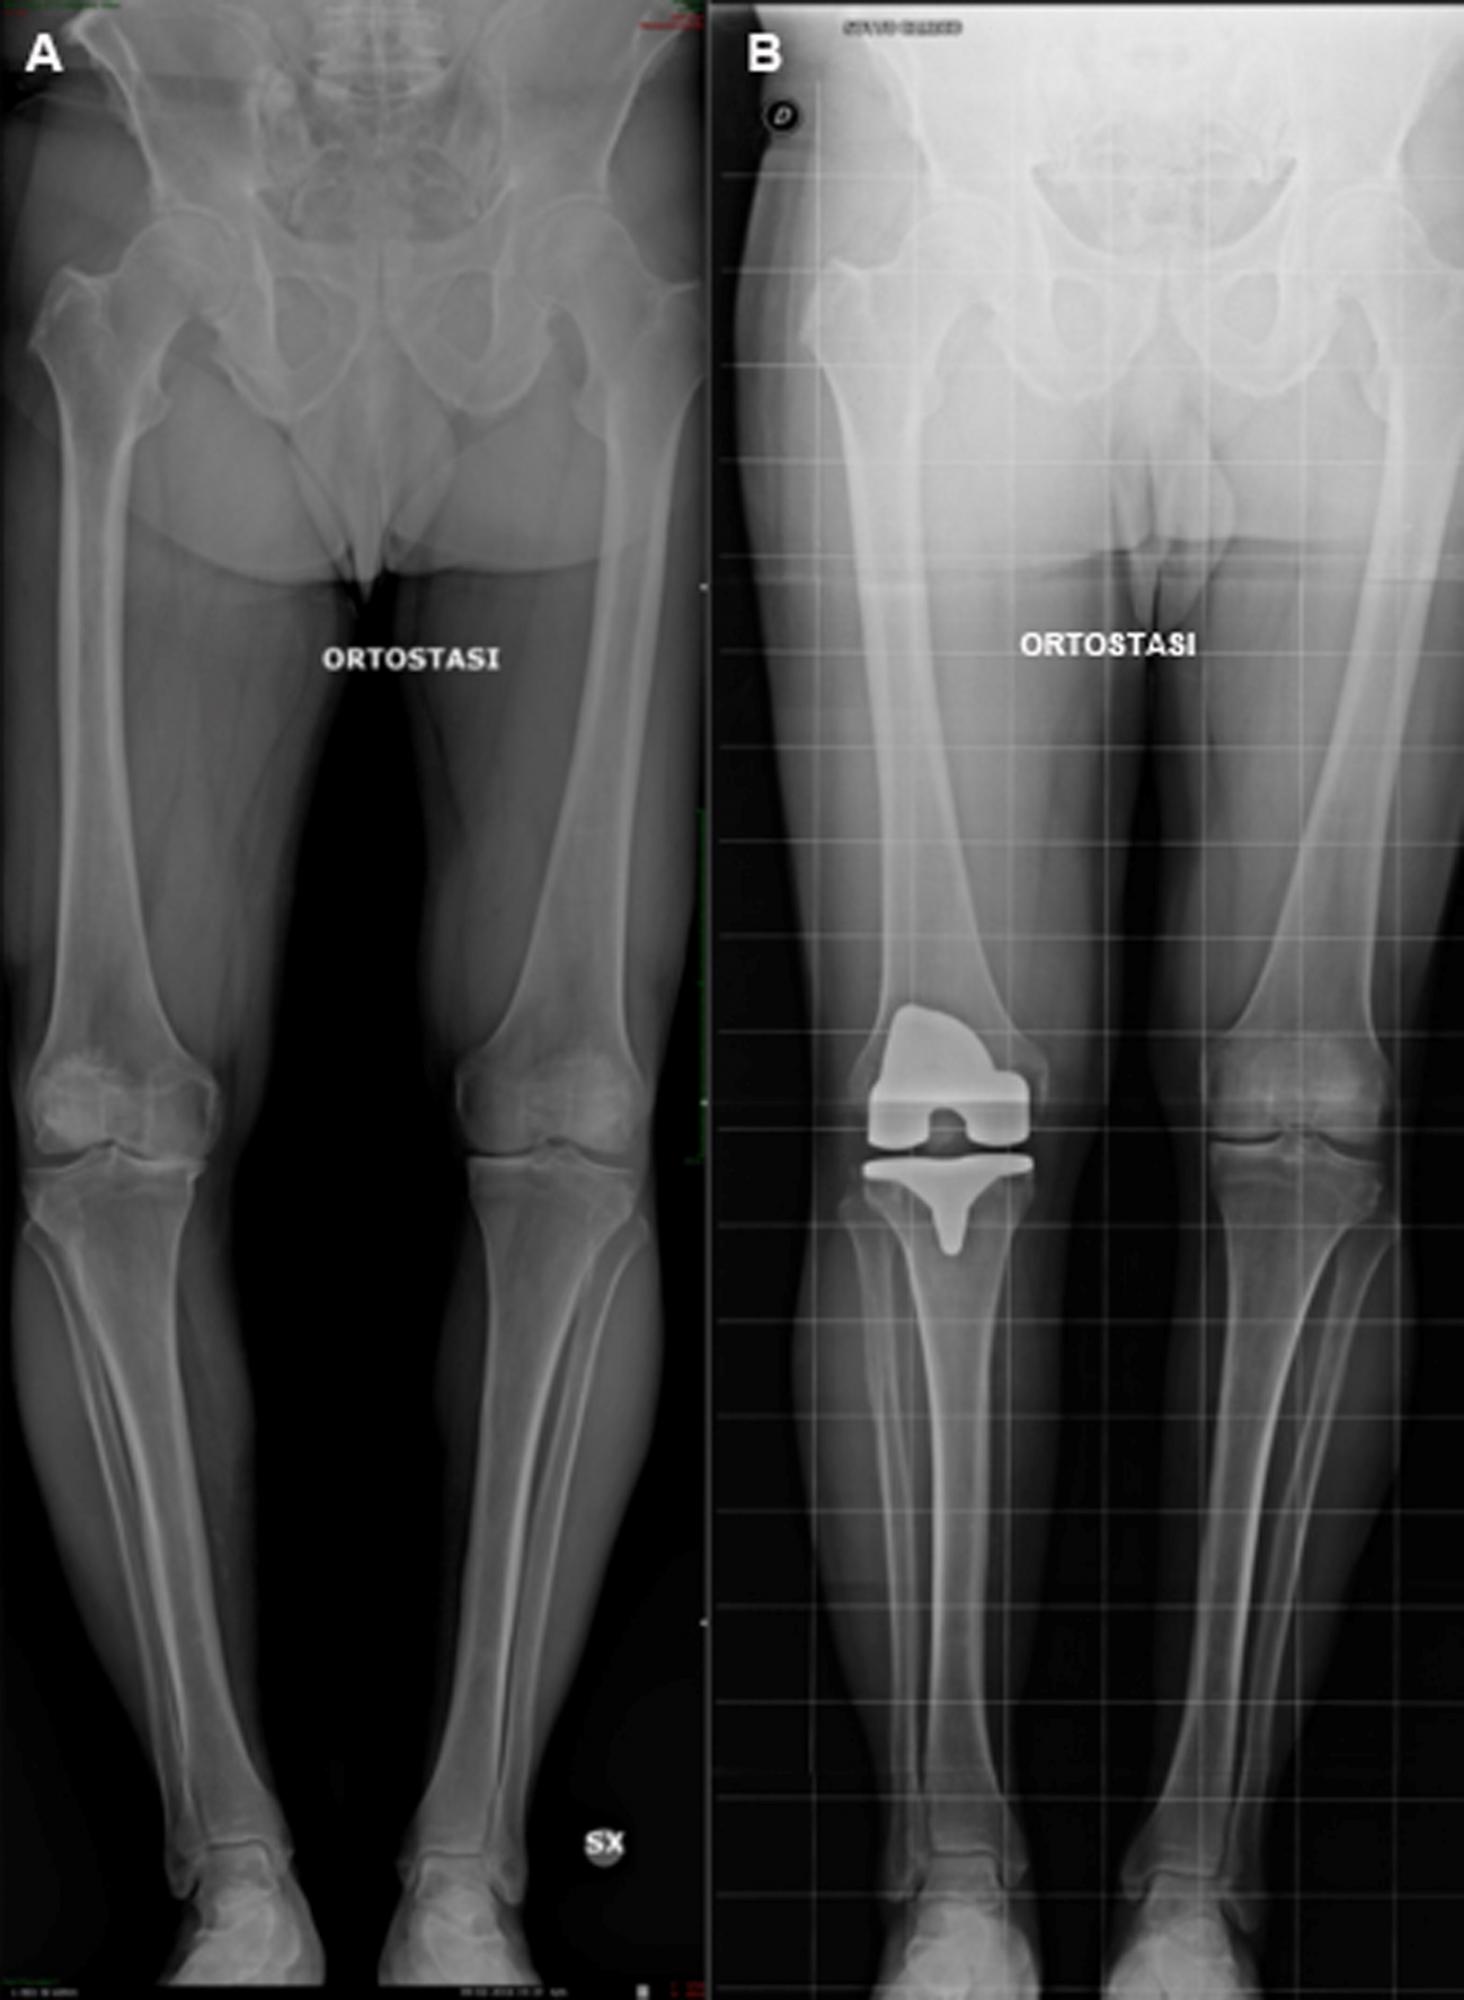

- Deformità del ginocchio: un ginocchio che è diventato flesso e non si estende più (risultato di una grave artrosi) e/o un ginocchio deformato verso l'interno (varo) o verso l'esterno (valgo) (Fig. 3). In questi casi la chirurgia protesica è in grado di riallineare gli arti.

Nella protesi totale del ginocchio (Fig. 4 e 5) vengono sostituite con parti metalliche le superfici di cartilagine danneggiate e una piccola quantità di osso sottostante alle estremità del femore e della tibia di tutto il ginocchio. Le parti metalliche generalmente vengono cementate all'osso con uno speciale cemento. Un inserto di plastica speciale molto resistente viene inserito tra le componenti metalliche per creare una superficie di scorrimento liscia. La superficie inferiore della rotula viene tagliata e sostituita con un bottone di plastica che viene anch’esso cementato. Alcuni chirurghi non protesizzano la rotula o lo fanno a seconda del caso, altri (come noi) la protesizzano sempre: non vi è evidenza scientifica in letteratura che dimostri la superiorità di una scelta rispetto all'altra quindi la scelta di protesizzare la rotula o meno dipenderà essenzialmente dall'esperienza del singolo Chirurgo.

Nella protesi monocompartimentale del ginocchio (Fig. 5 e 6) vengono sostituite con parti metalliche le superfici di cartilagine danneggiate e una piccola quantità di osso sottostante alle estremità del femore e della tibia solo di un compartimento (mediale o laterale) del ginocchio. I legamenti del ginocchio non vengono sacrificati. Questa protesi è meno invasiva di quella totale (4), consente un recupero più veloce ma può essere utilizzata solo nei casi in cui l’artrosi non coinvolga gli altri compartimenti del ginocchio (compartimento contro-laterale e/o femoro rotuleo). Esistono anche protesi monocompartimentali di femoro-rotulea: queste vengono utilizzate in casi selezionati di artrosi a carico di questo compartimento.